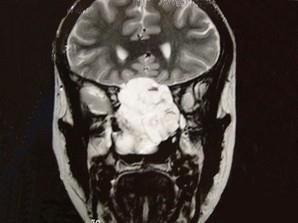

问题 女性,41岁,鼻腔流脓涕3年,鼻部面部肿胀1年,近来加重,MRI检查如图,请选择最可能诊断 ( )

选项 A、鼻咽癌 B、鼻腔血管瘤 C、鼻腔内出血 D、鼻腔软骨瘤 E、鼻腔内囊肿

答案 D